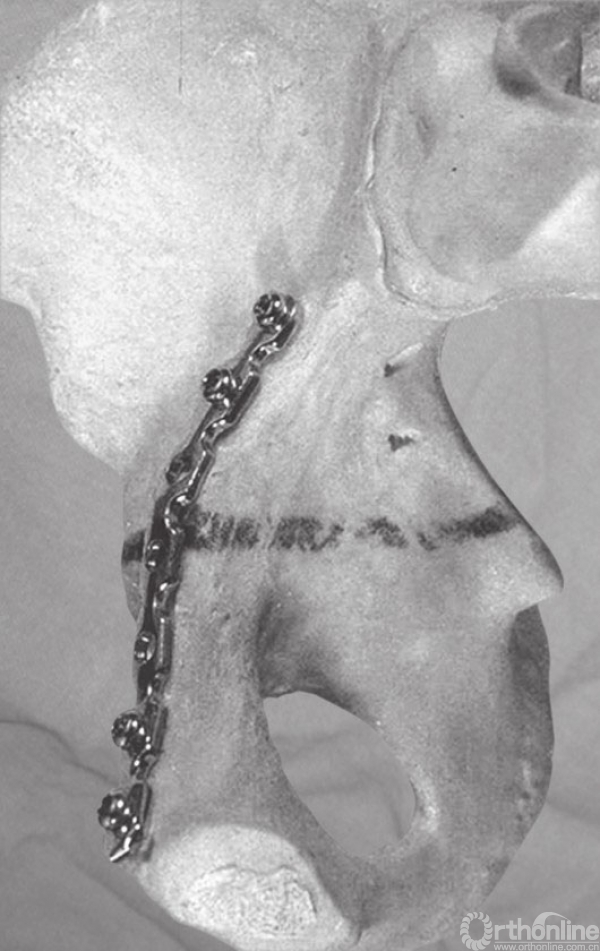

A和B(A)前方入路固定横行骨折;(B)骨盆内钢丝环扎

32岁男性患者,高处坠落伤后左侧髋臼出现横行骨折。采用髂腹股沟入路处理骨折。采用骨盆内钢丝环扎辅助复位和固定骨折。